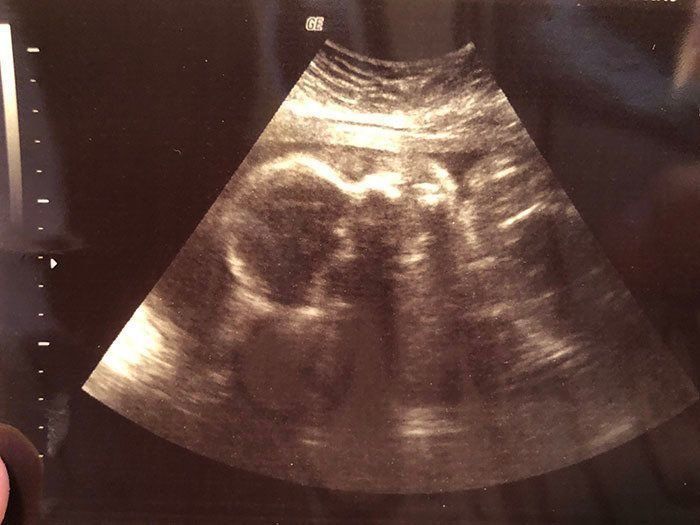

妊娠28週目 出産前に、家族で1泊旅行へ

妊娠28週目。この頃は、騒々しく感じるほどの胎動に耐え、体力を奪われる日々が続きました。そんな中、長男の誕生日のお祝いということで、一泊旅行へ出かけました。肺が圧迫されるのか、動くとすぐに息が上がってしまったため、移動には無料送迎などをフル活用しました。